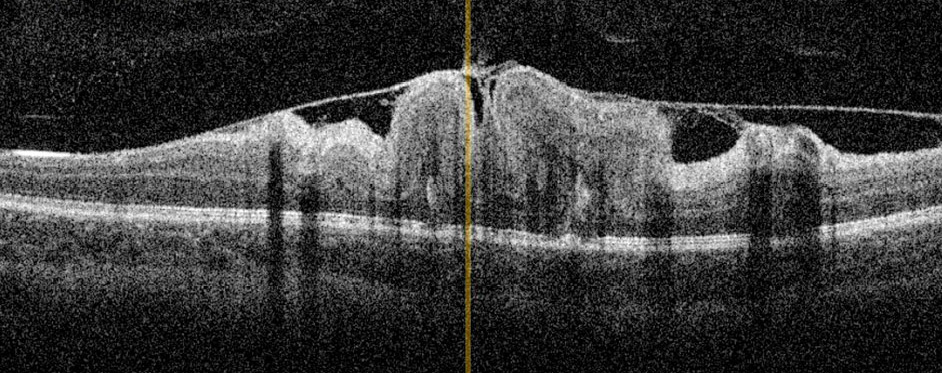

Рис. 2. Оптическая когерентная томограмма сетчатки ребёнка 8 лет с комбинированной гамартомой сетчатки и ретинального пигментного эпителия: деформация витреоретинального профиля макулярной зоны, утолщение и дезорганизация слоёв сетчатки с формированием складок, эпиретинальная мембрана. Максимально корригированная острота зрения 0,15.

Fig. 2. Optical coherence tomography (OCT) of the retina in an 8-year-old child with combined hamartoma of the retina and retinal pigment epithelium: deformation of the vitreoretinal profile in the macular zone, thickening and disorganization of retinal layers with fold formation, epiretinal membrane. Best corrected visual acuity (BCVA) 0.15.

По данным ОКТ, максимальная толщина сетчатки в зоне гамартомы варьировала от 476 до 841 мкм (в среднем 691). ЭРМ определяли во всех случаях. Выраженный тракционный синдром, характеризующийся наличием складок сетчатки вследствие тангенциального натяжения, диагностирован у 10 детей [в 11 из 13 глаз с комбинированной гамартомой макулярной локализации (84,6%)] (рис. 2). В двух глазах с макулярной и перипапиллярной локализацией гамартомы отмечали незначительную тракцию сетчатки в центральной зоне со стороны ЭРМ (рис. 3).

Среди других характерных признаков ОКТ комбинированной гамартомы сетчатки и РПЭ мы выявили:

- в шести глазах мини-пики — пилообразный рисунок витреоретинального контура или наружного плексиформного слоя [11] (рис. 4);

- в семи глазах макси-пики — складки сетчатки по всей толщине [11] (рис. 5);

- в двух глазах «знак омега» — образуется за счёт глубоких складок сетчатки (двух макси-пиков), обусловлен сочетанным воздействием вертикальной тракции от наружного плексиформного слоя к внутренним слоям сетчатки и тангенциальной тракции вследствие сокращения ЭРМ [12] (рис. 6);

- в четырёх глазах «зубы акулы» — треугольные гиперрефлективные изменения в наружном ядерном слое [13] (рис. 7).